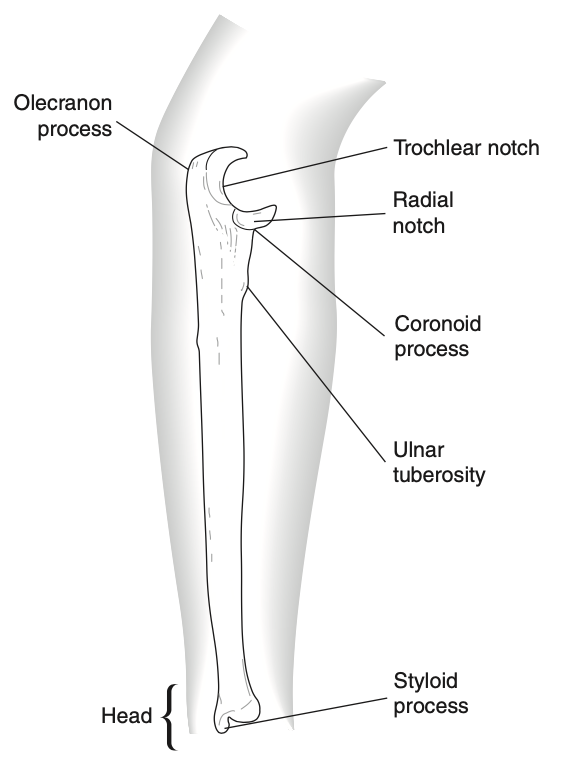

- Gồm 3 xương: xương cánh tay (đầu dưới), xương quay và xương trụ

- Đầu gần của Xương trụ lớn hơn nhiều đầu gần Xương quay

- Đầu xa Xương quay lớn hơn nhiều đầu xa Xương trụ